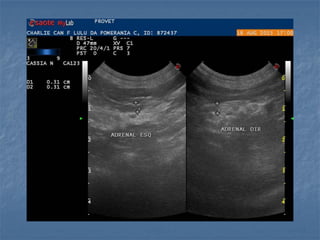

 Em cães

 Formato (parece o formato do cão!):

- Esquerda tem formato de amendoim (alongada)

- Direita tem formato de vírgula

 Ecogenicidade: hipoecoica em relação a gordura

adjacente, com cortical e medular distintas

 Dimensões (cães):

- 2,0 a 3,0cm x 0,5cm

- Idosos até 0,74cm

- máximo diâmetro no

pólo caudal (melhor

sensibilidade e

especificidade)

Barthez et al.,1998